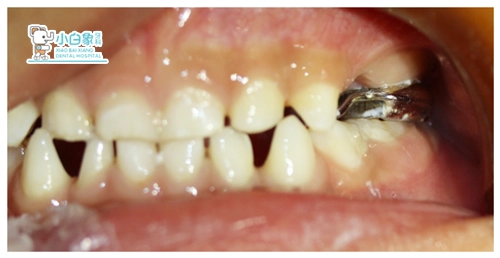

主诉:左上乳牙缺失数月。

检查:左上IV伤口愈合良好,牙龈无红肿

诊断:左上IV缺失

治疗计划:佩戴间隙保持器